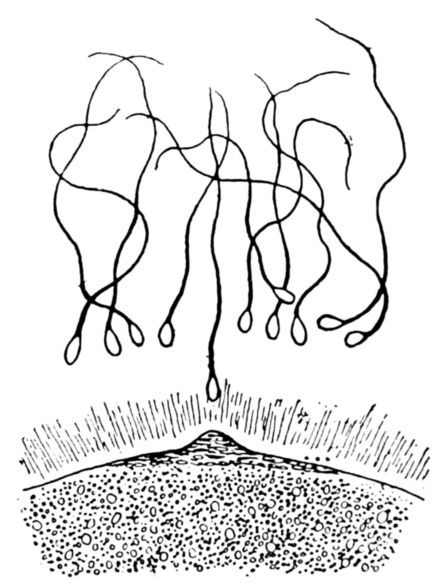

| 17. | Diagram of human spermatozoa | 61 |